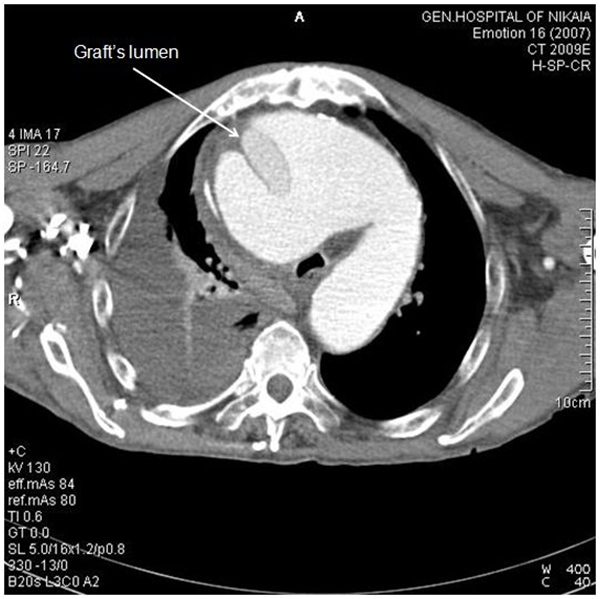

Due to patient’s history, a CT-angiography was immediately performed, which showed a massive perigraft aneurysm, 9x9.5 cm in maximum diameter, extended to the arch, compressing superior vena cava (SVC), brachiocephalic artery, right coronary artery (RCA), and graft partially detached from distal anastomosis, but within the aneurysmal sac Figure (2-7). The aneurysm was probably formed by a leakage at distal anastomosis, between the graft and the native aortic wall which was wrapped around it. A large right pleural effusion was also obvious. However, active leakage of the contrast agent from aneurysmal sac to the surrounding tissues was not observed at that point.

Figure 4 CT-angiography, anterior frontal view: Graft was partially detached from distal anastomosis (white arrowhead), resulting in perigraft leakage. Epiaortic vessels are visualized in this view. Proximal edge of the graft seems to be firmly attached to left ventricular outflow tract.